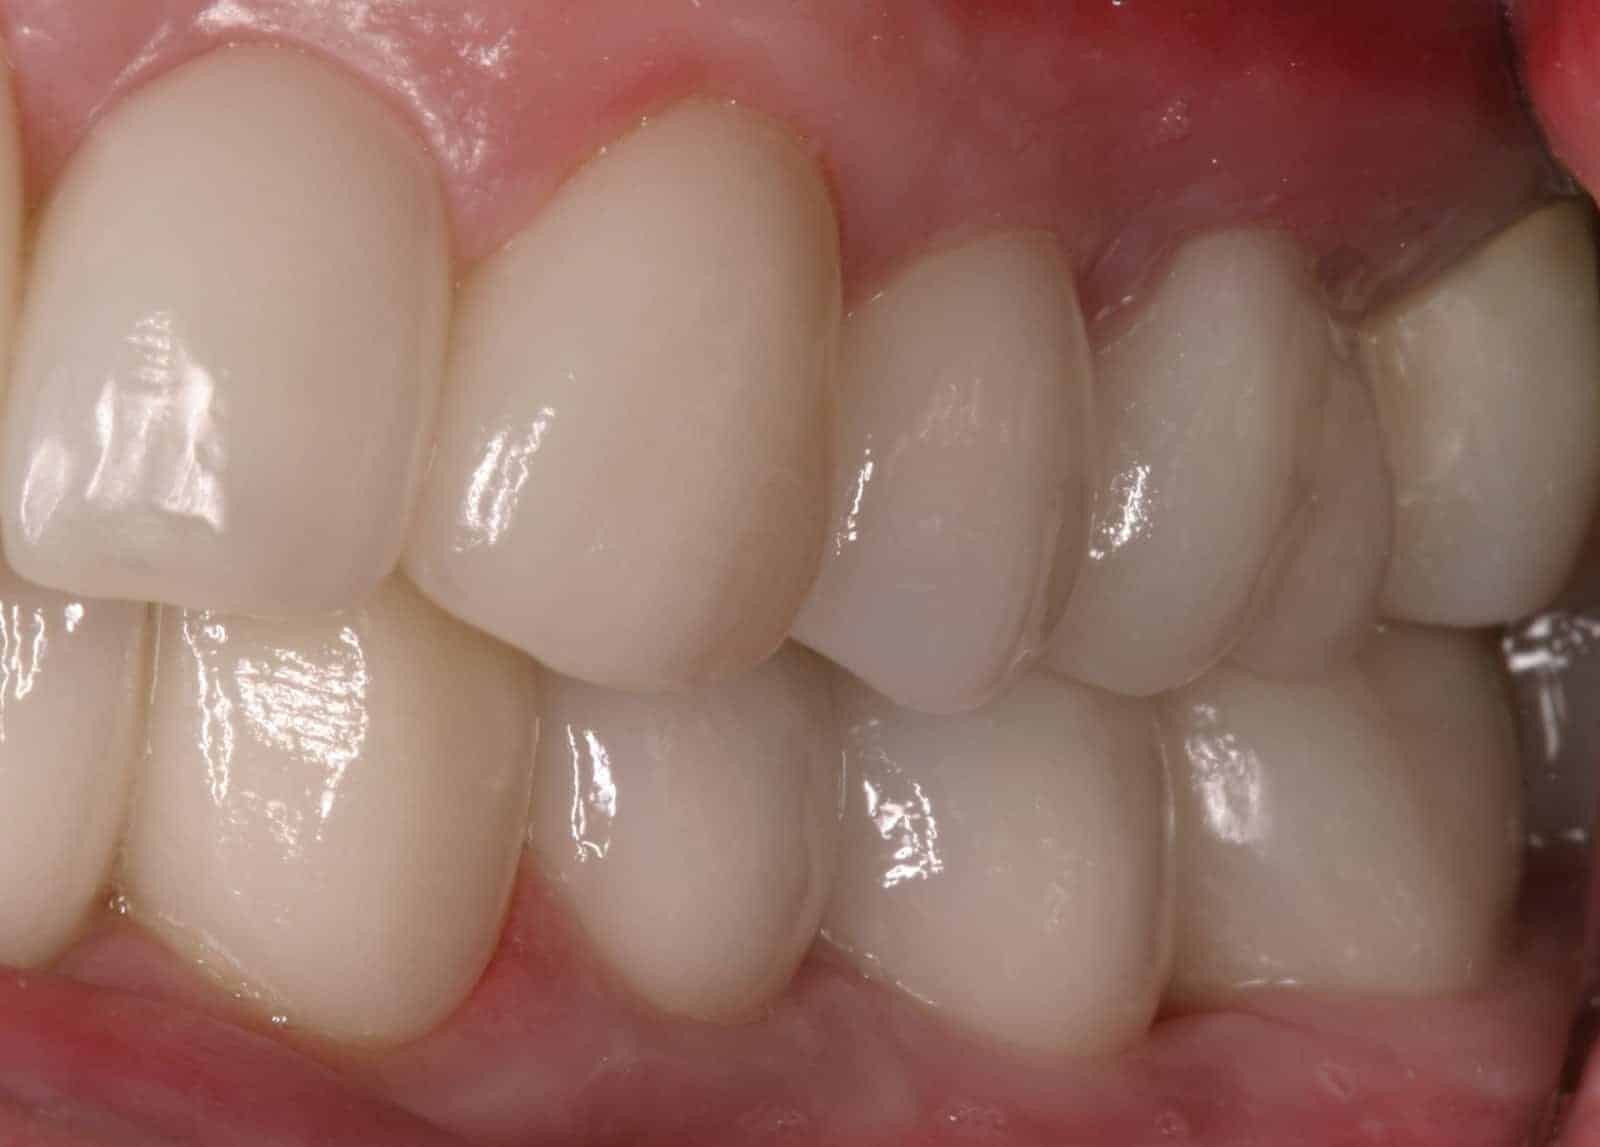

After:Â Implants were then placed by the team oral surgeon utilizing surgical guides fabricated by Dr. Leopardi. Dr. Leopardi then performed a complete dental (full mouth) rehabilitation: full coverage, conservative bonded porcelain restorations on natural teeth; all ceramic implant restorations on the upper lateral incisor implants (sited 7 and 10), porcelain fused to gold implant restorations on implants 3, 14, 19, 21, 23, 25, 28 and 29, at increased occlusal vertical dimension. Patient was restored to full function and aesthetics, significantly improving quality of life.